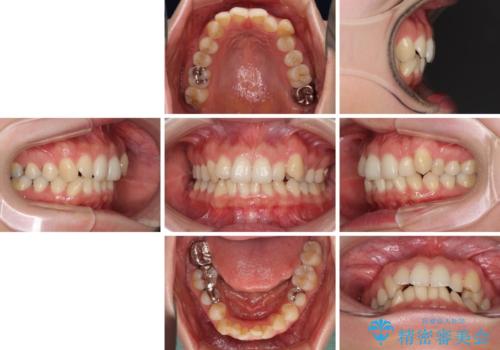

- 上下の前歯のデコボコを治したいとのことで来院された患者様です。

仕事柄、アジアの3つの国と地域を行き来するため、ワイヤー装置での治療は難しいと考えられました。

上下顎ともにIPR(歯と歯の間を削る)と歯列全体の拡大によって叢生が解消するように設計し、インビザラインにより治療を行うこととしました。

1日22時間の装着時間を守ってくださったので、比較的早く治療を終える予定でしたが、各国での入国制限が厳しくなり、帰国のタイミングに合わせてのんびりと治療を進めることとなってしまい、やや長期間の治療となりました。